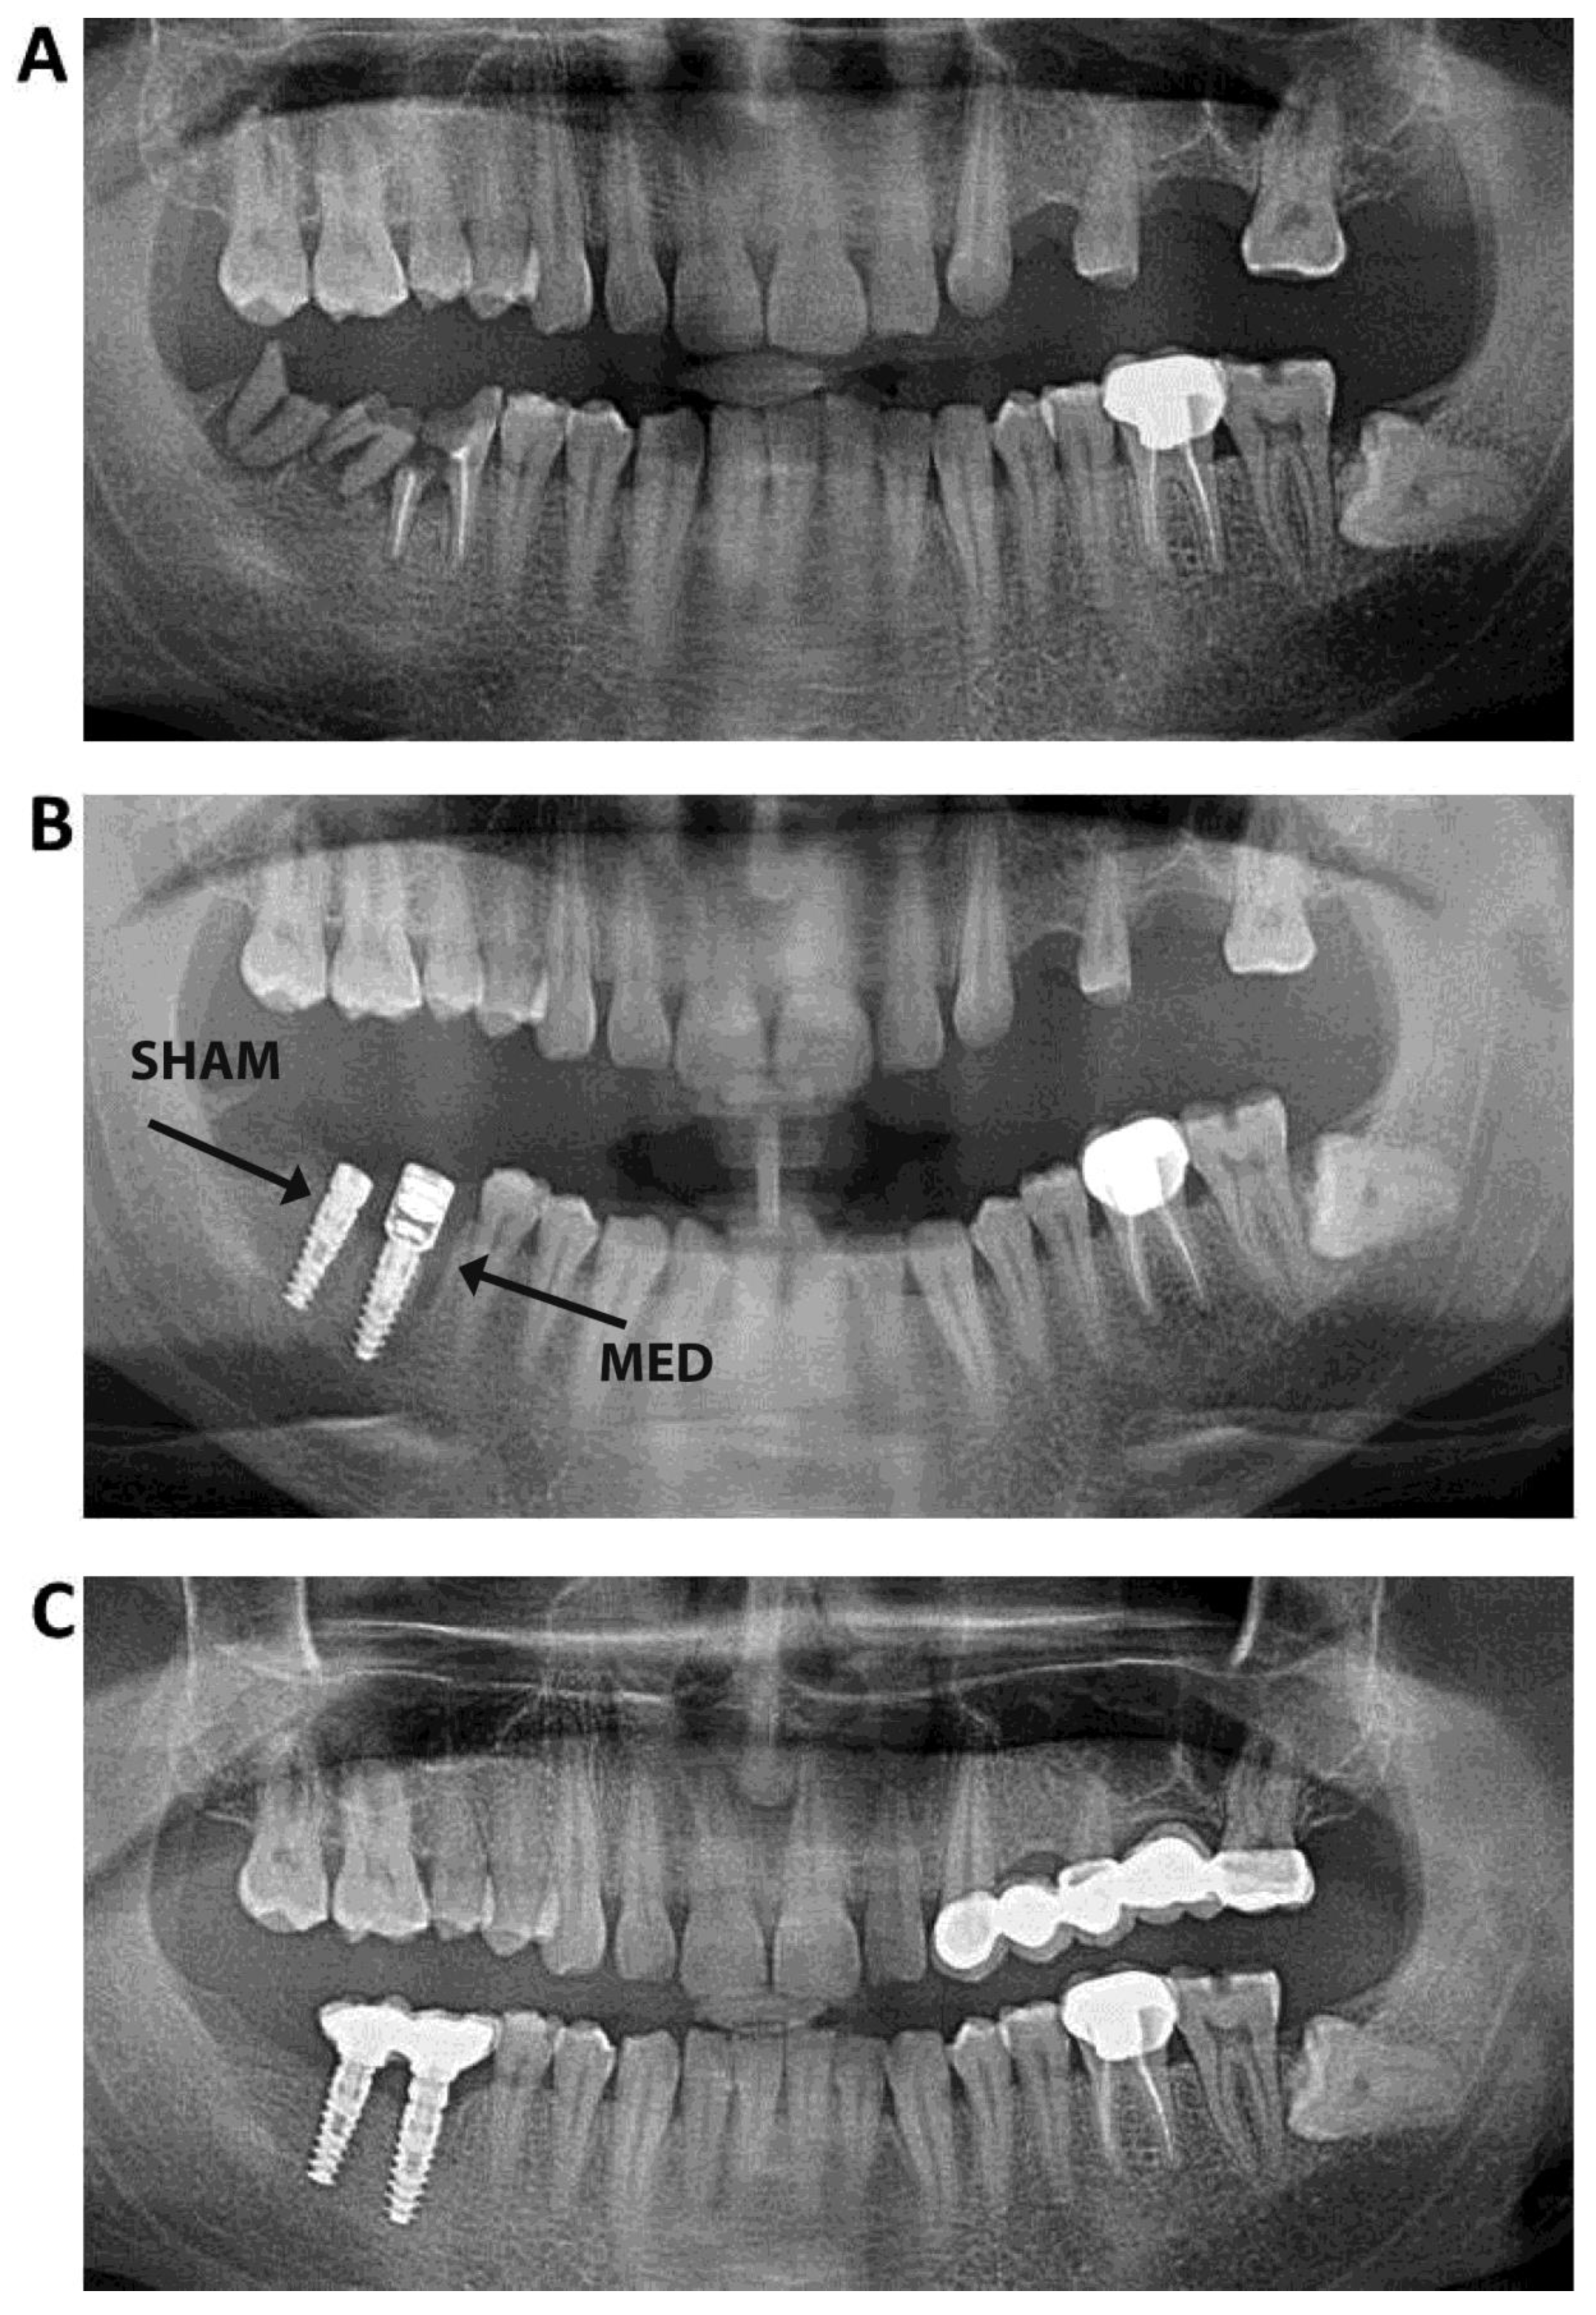

1. Introduction

2. Materials and Methods

2.1. Surgical Procedures

2.3. Radiographic Evaluation

3.2. Radiographic Evaluation